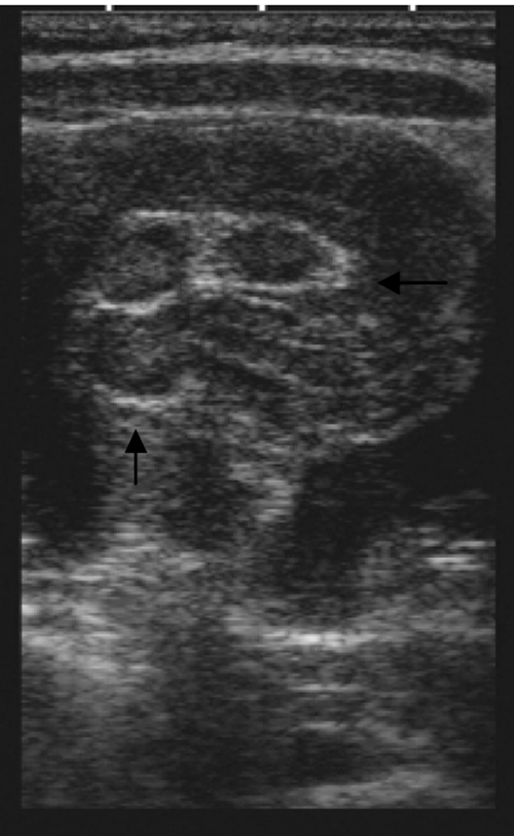

Figure 1. Intussusception “pseudokidney sign” described on pediatric patient in 2009

- Kairam N, Kaiafis C, Shih R. Diagnosis of pediatric intussusception by an emergency physician-performed bedside ultrasound: a case report. Pediatr Emerg Care. 2009;25(3):77-180.